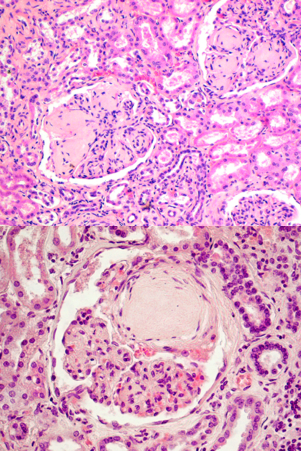

identify

Rapidly progressive (crescentic) glomerulonephritis (360)